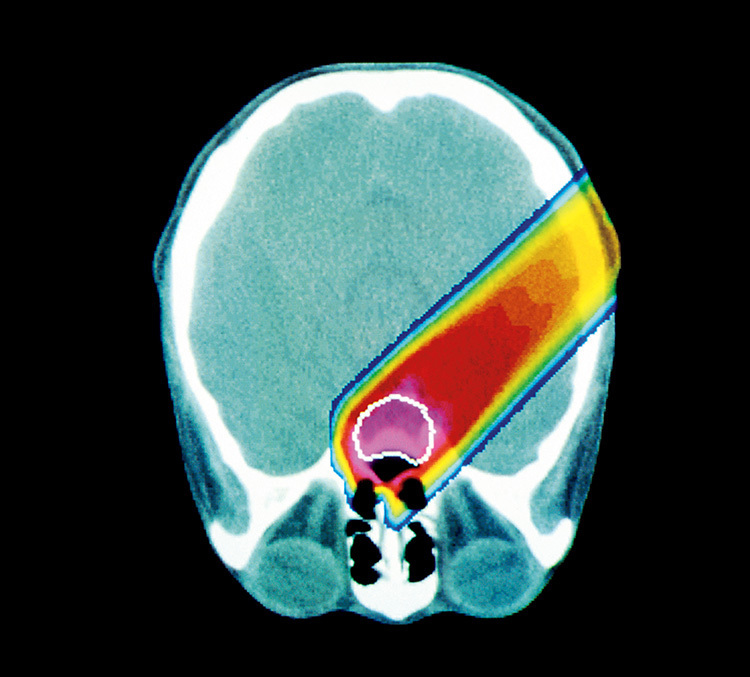

In recent years, she has focused on proton therapy. When proton beams are used, the depth of the irradiation can be controlled to stop it from going any deeper than the lesion. That mitigates side effects on normal cells by allowing the irradiation to be concentrated more on the cancer cells. The treatment is attracting attention as being less burdensome on the body for elderly cancer patients with declining organ function and multiple health conditions. Proton therapy also reduces the risk for second malignancies (the development of different cancer growths long after treatment) in children, who are more susceptible to radiation exposure.

As proton therapy controls the depth of the irradiation to stop precisely at the cancer cells, it reduces side effects on neighboring normal cells. Less burdensome on the body, it thus holds promise as a treatment that offers better quality of life.